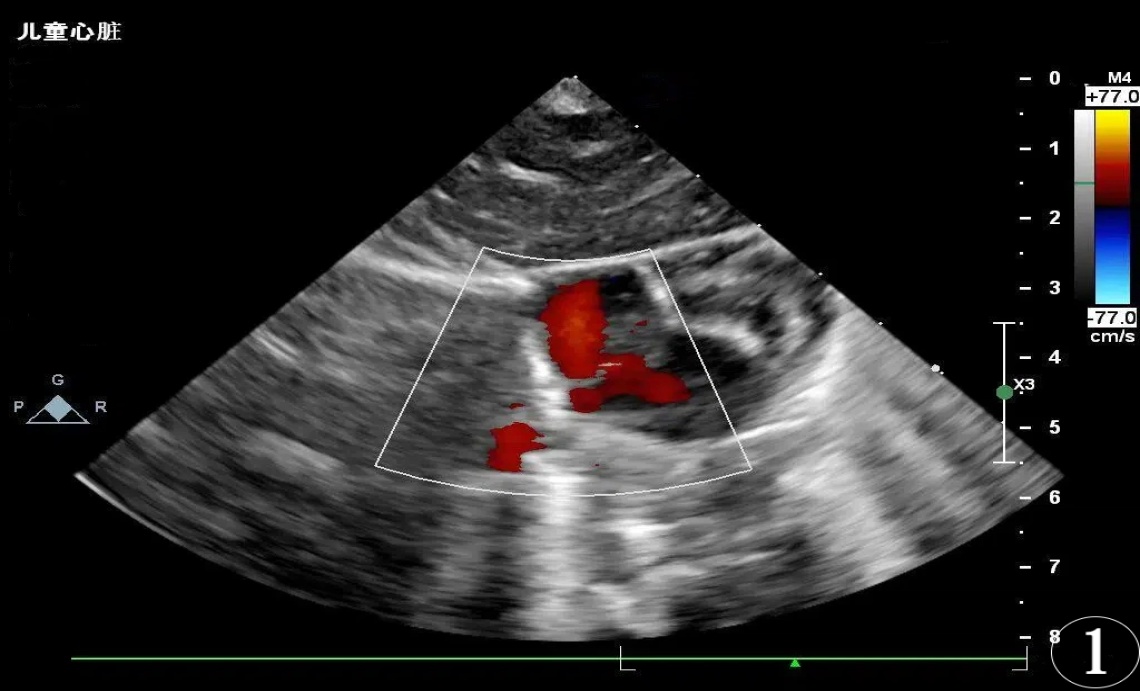

患儿,男,胎龄36周,出生体重3160 g,单胎,无窒息复苏史。系第2胎第2产,于暨南大学附属第一医院产科经阴道分娩娩出,出生时羊水清,自然啼哭,肤色稍青紫,反应、肌张力可、听诊心率 > 100次/分,Apgar评分:生后1 min为9分(肤色扣1分)、5 min、10 min均为10分。脐带水肿,绕颈一周,胎膜、胎盘无异常。血糖:3.0 mmol/L。血型:O型Rh阳性。其母血型为O型Rh阳性,妊娠期糖尿病,无感染史及用药史;其父血型为A型Rh不详;父母双方均否认地中海贫血及蚕豆病。生后予完善三大常规、生化肝功、感染二项、血气分析、DIC等多项检查。因患儿无相关临床表现,且母孕期无明确感染史,新生儿期未行TORCH血清学筛查(包括弓形虫、风疹病毒、巨细胞病毒、单纯疱疹病毒等)。其中,血常规 + 感染指标(出生第1天):超敏C反应蛋白0.33 mg/L,血小板计数204.00 × 109/L,白细胞计数20.23 × 109/L。血气分析(出生第1天):红细胞压积58%,氧饱和度90.2%。DIC检测:D-二聚体2130 ng/ml (FEU),纤维蛋白原2.98 g/l。降钙素原0.299 ng/mL。血常规、生化检查、肝功能、粪便常规 + OB、尿液分析均未见明显异常。血常规 + 感染指标(出生第3天):超敏C反应蛋白2.29 mg/L,血小板计数194.00 × 109/L,白细胞计数26.03 × 109/L。患儿生后查胆红素生理性升高,新生儿科予常规护理及蓝光照射退黄。生后查心脏彩超提示卵圆孔未闭(Patent Foramen Ovale, PFO) 1.9 mm,动脉导管未闭(Patent Ductus Arteriosus, PDA) 1.5 mm (见图1图2)。生后颅腔彩超检查提示颅脑回声及血流未见明显异常。听力筛查大致正常。结合患儿的症状、体征及辅助检查,临床诊断:早产儿、卵圆孔未闭、动脉导管未闭、胎儿和新生儿受母体情况的影响(妊娠期糖尿病)、胎儿和新生儿受脐带其他情况的影响(脐带水肿,绕颈一周)。该患儿出生后24小时内于暨南大学附属第一医院眼科行新生儿眼底筛查,眼底数码相机(RetCam III)检查可见:双眼视网膜平伏,视盘及黄斑发育可,双眼眼底颞上、颞下、鼻上、鼻下四个象限均可见大量类圆形或圆形出血灶散在分布,出血灶中心呈白色点状,约20~25处,最大出血灶直径可达1.5 PD,主要分布在视网膜后极部;视网膜血管鼻侧已达睫状体周边部,颞侧未达睫状体周边部。(见图3图4)。患儿双眼眼底检查未见早产儿视网膜病变(Retinopathy of Prematurity, ROP)体征(按2014年版指南判定标准),但双眼可见大量Roth斑,予常规表面护理及随访观察。计划随访时间为第1周,实际完成于第2周。生后第2周我科随访,该患儿眼部检查:双眼角膜透明,瞳孔等大等圆,双眼眼底视网膜平伏,视盘边界清晰,血管走行正常,双眼周边视网膜已基本血管化,黄斑发育良好,后极部及周边部均未见明显渗出及出血灶(见图5)。生后2月余于我院门诊复查心脏彩超提示卵圆孔及动脉导管均闭合,心内结构及血流未见异常(见图6图7)。

Figure 1. The infant’s cardiac ultrasound examination: Patent Foramen Ovale. Color Doppler Flow Imaging (CDFI) reveals a cleft in the mid-portion of the atrial septum, with a blood flow jet passing from the left atrium through the atrial septum into the right atrium. The width of the blood flow jet is approximately 1.9 mm

1. 示患儿心脏彩超检查:卵圆孔未闭。彩色多普勒血流成像(Color Doppler Flow Imaging, CDFI)房间隔中部见一裂隙,见血流束自左房穿过房间隔进入右房,血流束宽约1.9 mm